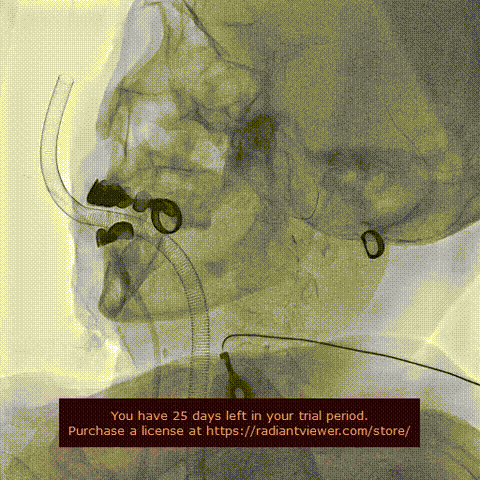

左颈动脉放入脑保护伞

脑保护伞回收

术后主动脉弓部造影

在影像、超声的共同指引下,术者团队通过调整输送系统至最佳位置实现精准释放,患者跨瓣压差即刻显著下降至3mmhg。再行主动脉造影提示瓣膜置入位置良好、形态完整,超声提示未见明显瓣周漏。手术圆满成功。